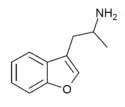

List of substituted α-alkyltryptamines

α-Alkyltryptamines are a group of substituted tryptamines which possess an alkyl group, such as a methyl or ethyl group, attached at the alpha carbon, and in most cases no substitution on the amine nitrogen.[17][18][19] α-Alkylation of tryptamine makes it much more metabolically stable and resistant to degradation by monoamine oxidase, resulting in increased potency and greatly lengthened half-life.[19] This is analogous to α-methylation of phenethylamine into amphetamine.[19]

αMT | 1-(1H-Indol-3-yl)propan-2-amine | 299-26-3 |